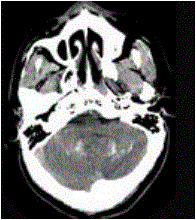

问题 男,52岁,无明显不适,CT检查如图所示,最可能的诊断为()

选项 A.脑血管畸形 B.结节性硬化 C.甲状旁腺低功能下 D.脑颜面血管瘤 E.转移瘤

答案 C